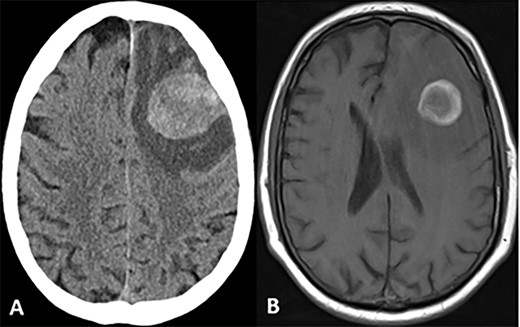

CASE

Spindle cell neoplasm with pleomorphic epithelioid features, multinucleation, mitoses and necrosis, involving pulmonary artery (A, B) and brain (C, D), H&E.